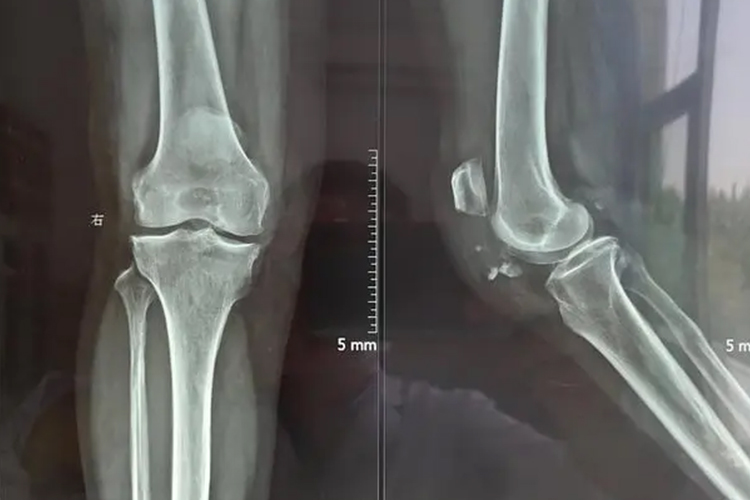

闭合伤:由局部出血及液体渗出所致,常伴有皮肤青紫、淤斑、血肿,伤后2-3日达到高峰。严重肿胀可致局部或远端肢体血供障碍。此外,如摔伤后局部皮肤完整,但是肿胀明显,也可能是发生膝关节的脱位,X线检查可以确诊。